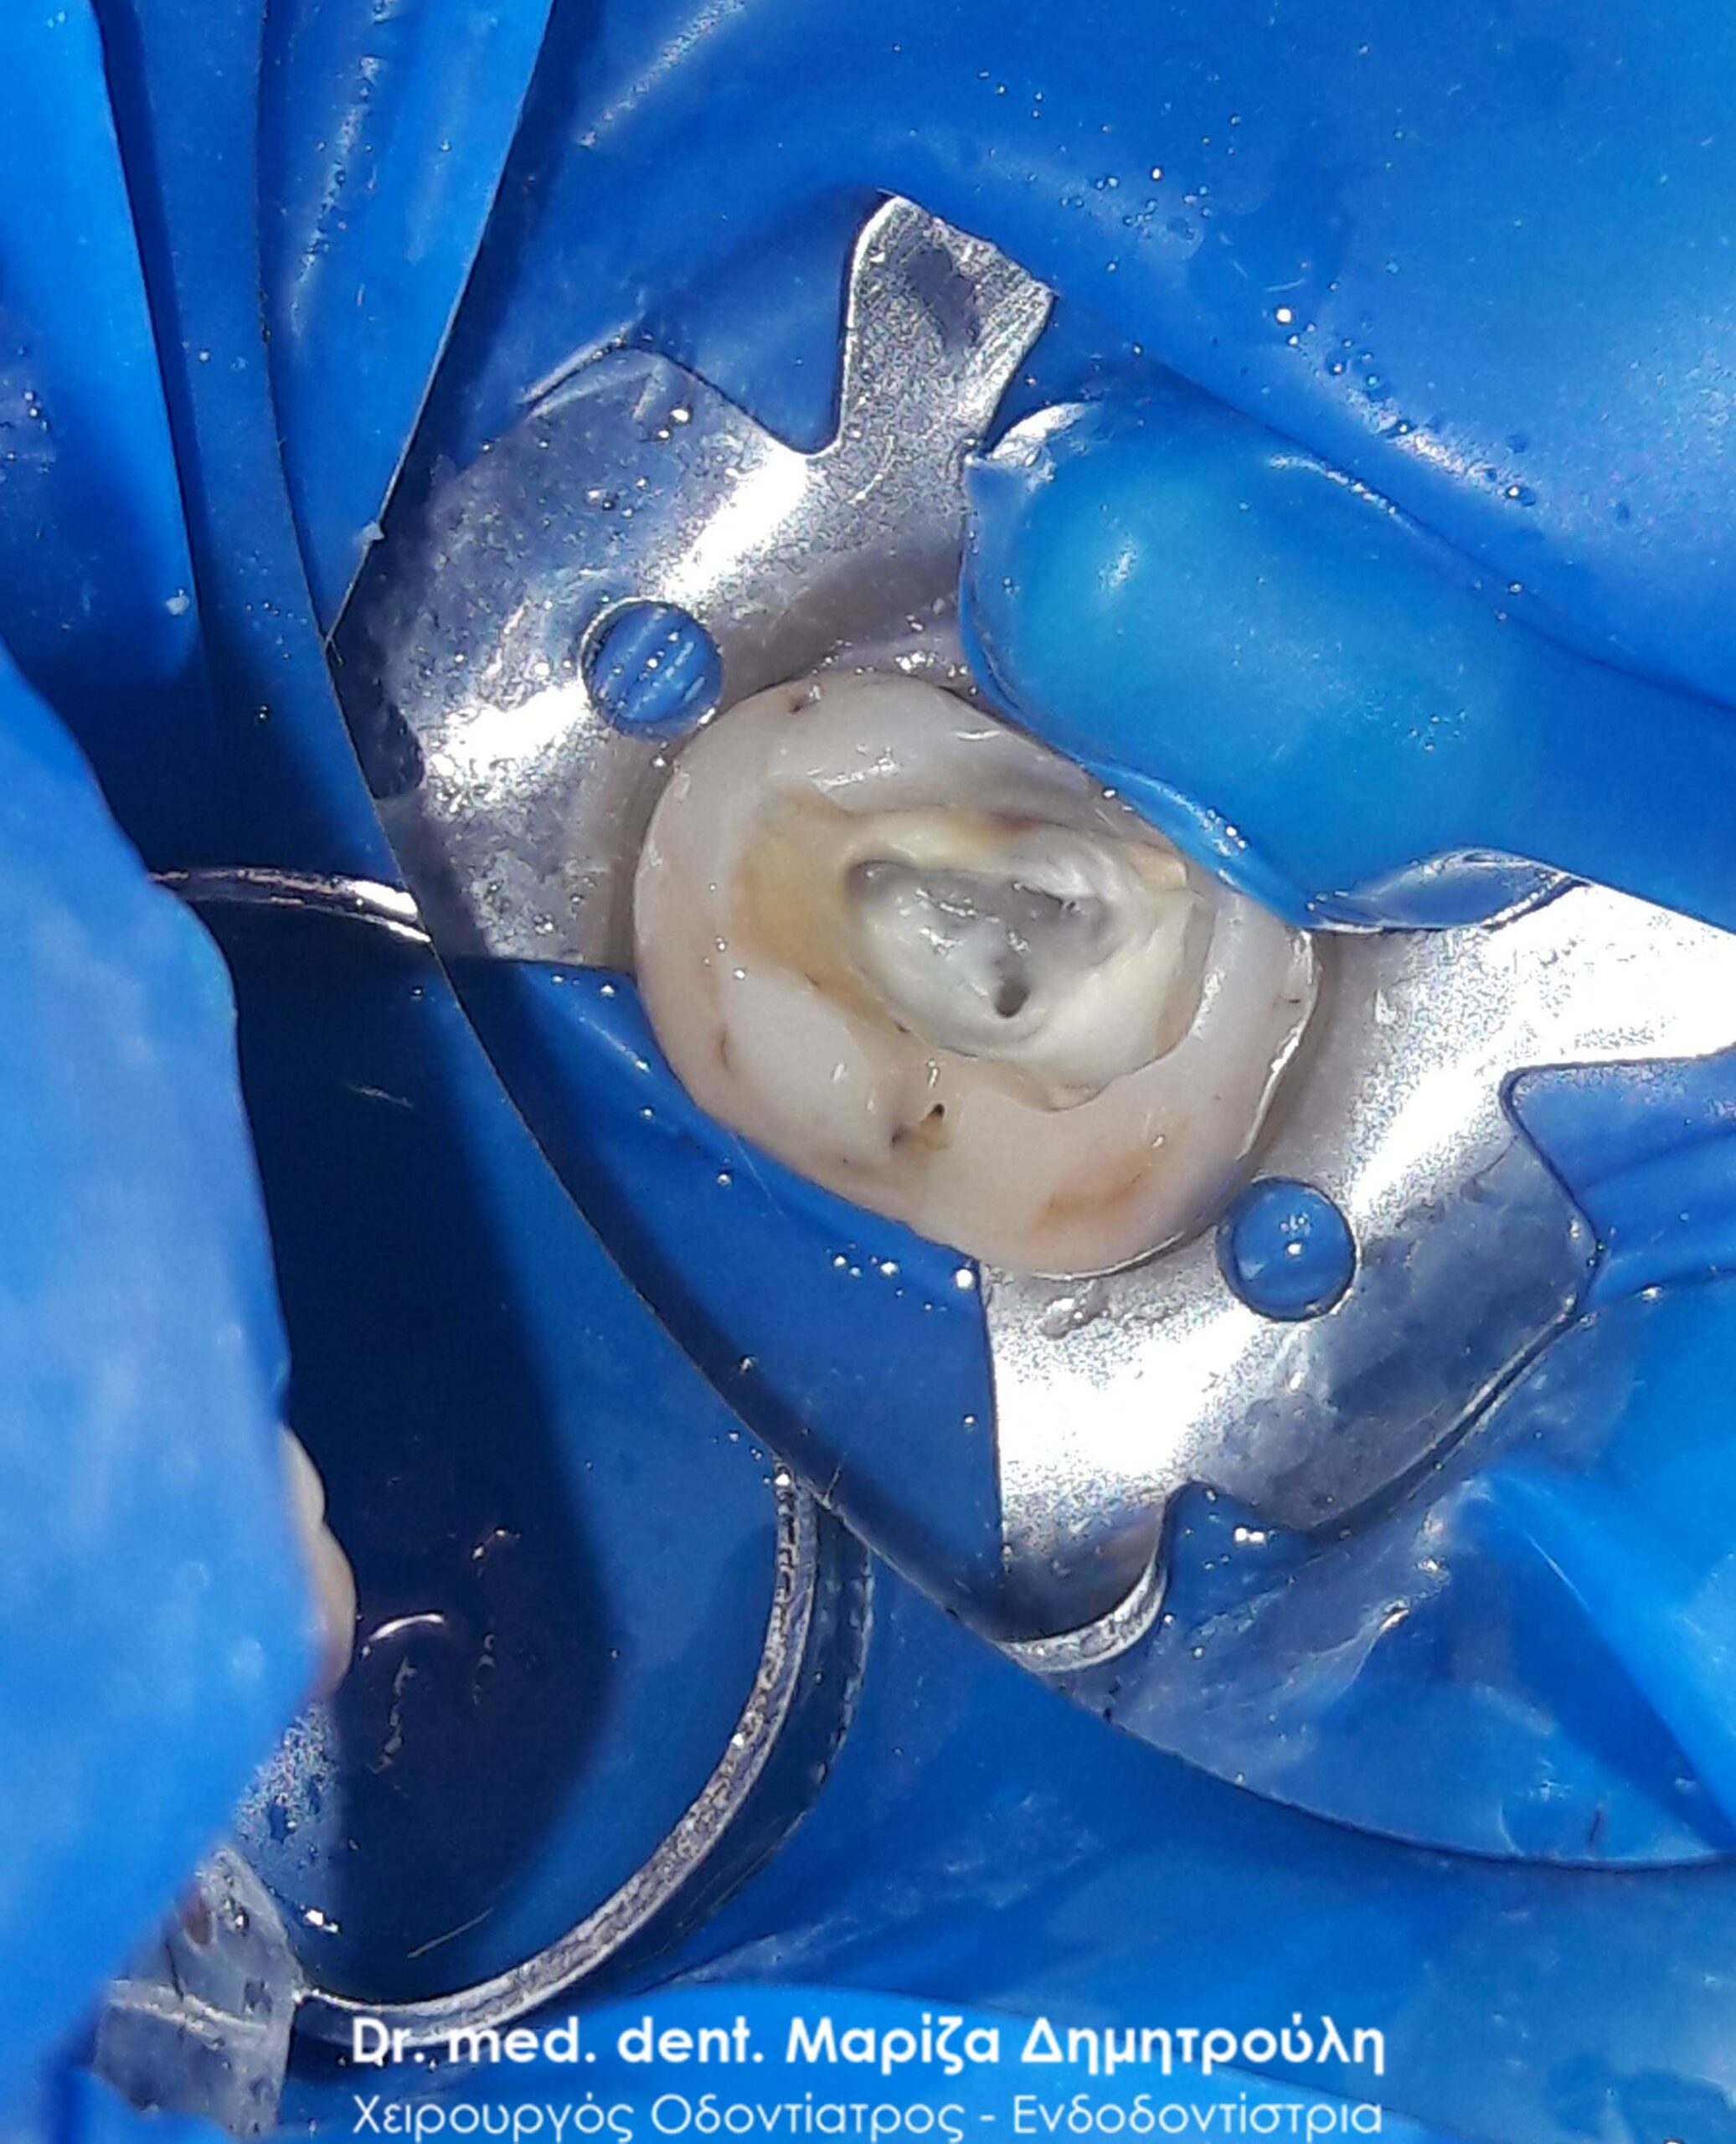

Clinical photo after the preparation of root canals